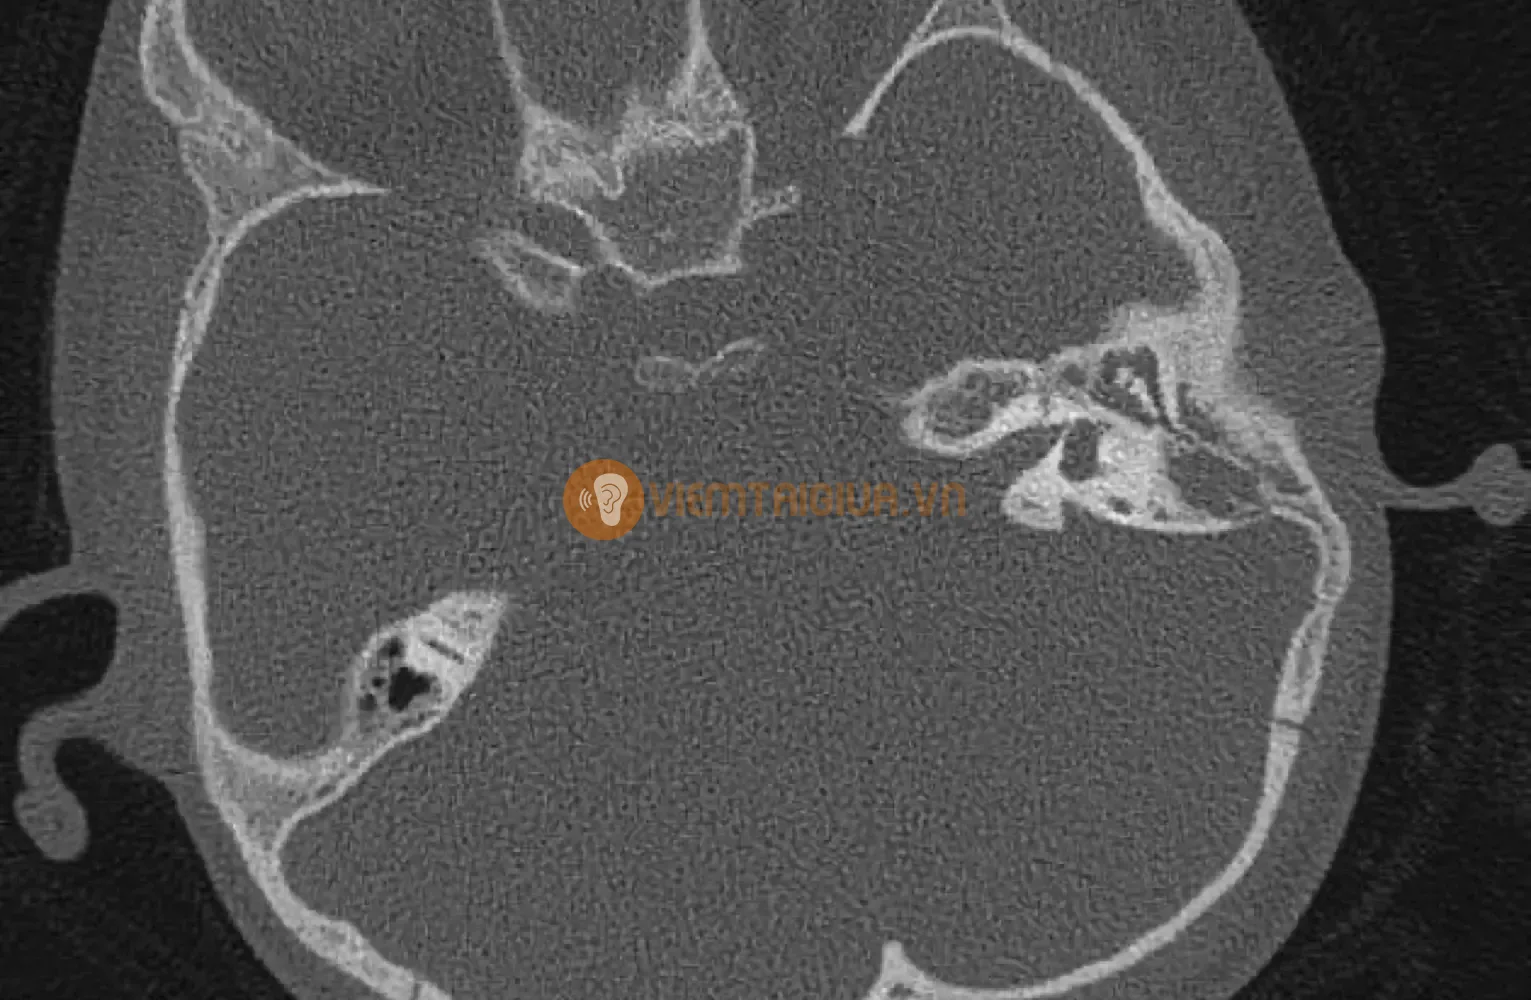

- CT scan (chụp cắt lớp vi tính): Đây là phương pháp hình ảnh chi tiết hơn giúp xác định mức độ lan rộng của nhiễm trùng và tình trạng tổn thương ở xương chũm.

6. Một số hình ảnh viêm xương chũm